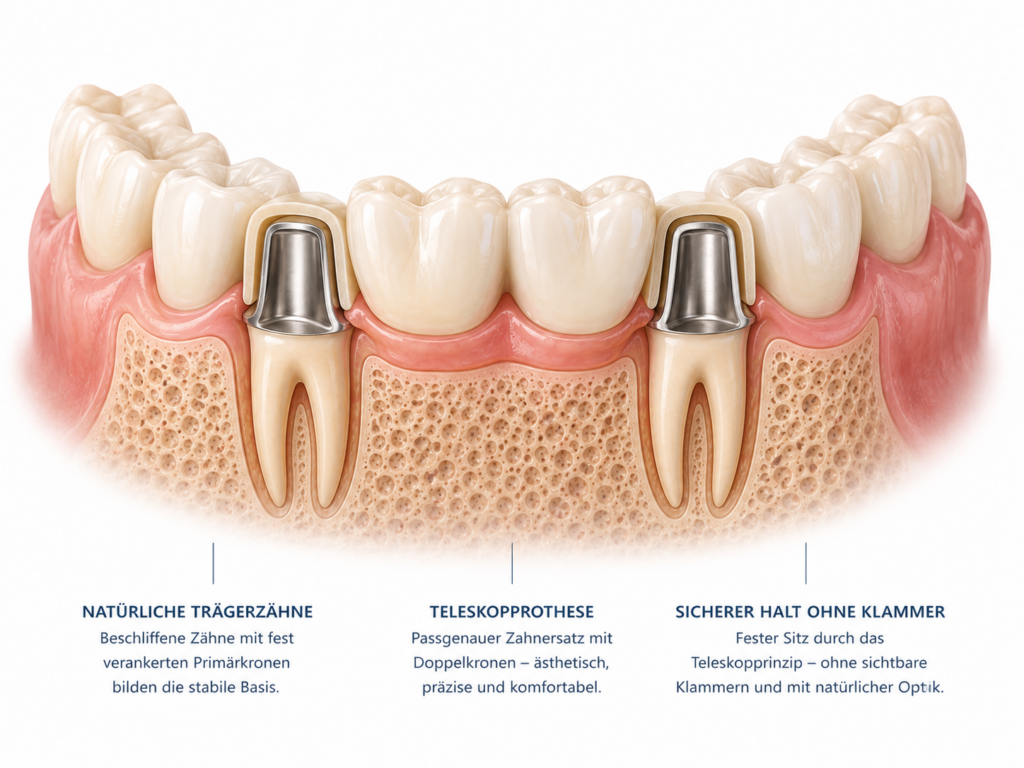

Herausnehmbarer Zahnersatz kommt zum Einsatz, wenn mehrere oder alle Zähne ersetzt werden müssen. Dazu zählen Teilprothesen, Teleskopprothesen und Vollprothesen. Sie lassen sich zur Reinigung herausnehmen und werden individuell an den Kiefer angepasst.

Wenn nur ein einzelner Zahn ersetzt werden muss, kann eine Krone oder eine Brücke infrage kommen. Fehlen mehrere Zähne, sind oft umfangreichere Lösungen notwendig – zum Beispiel herausnehmbarer Zahnersatz oder Zahnersatz auf Implantaten. Auch ästhetische Aspekte und der gewünschte Tragekomfort spielen eine wichtige Rolle.

Festsitzender Zahnersatz wie Kronen oder Brücken kann bei guter Pflege oft viele Jahre, teilweise sogar Jahrzehnte halten. Herausnehmbarer Zahnersatz hat in der Regel eine etwas kürzere Lebensdauer, da er stärker beansprucht wird und sich der Kiefer im Laufe der Zeit verändern kann.